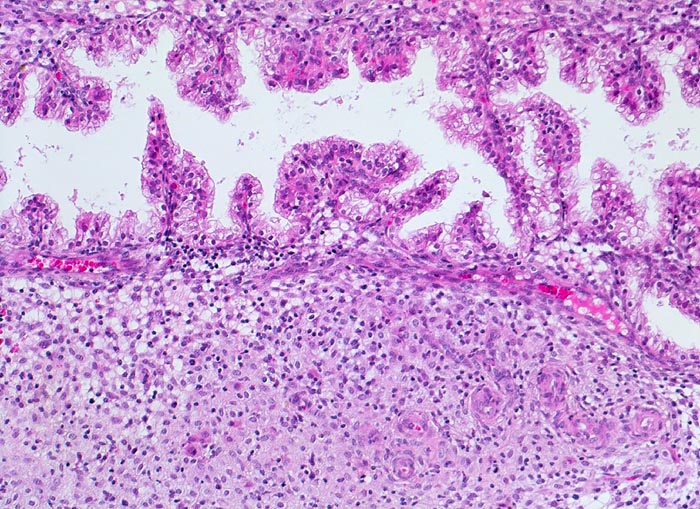

Endometrium in Sekretionsphase (11. Tag nach Ovulation)

Sägezahnartige Endometriumdrüsen. Klarzelliges hochprismatisches einreihiges Epithel mit apikaler Sekretion. Das Stroma ist grosszellig umgewandelt. Rechts unten im Bild Spiralarterien.